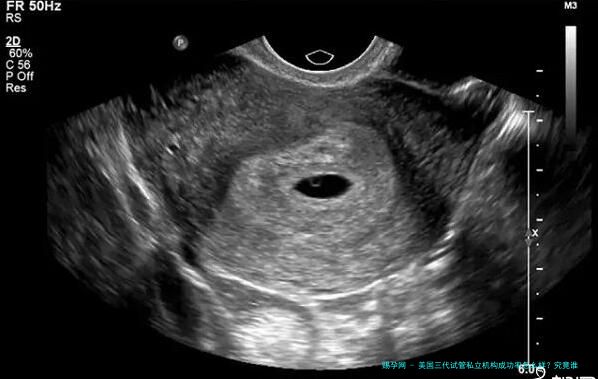

三代试管通过将孕妇卵子、男性精子和另外一个女性的助孕结合,然后将受精卵植入到孕妇子宫内实现妊娠。